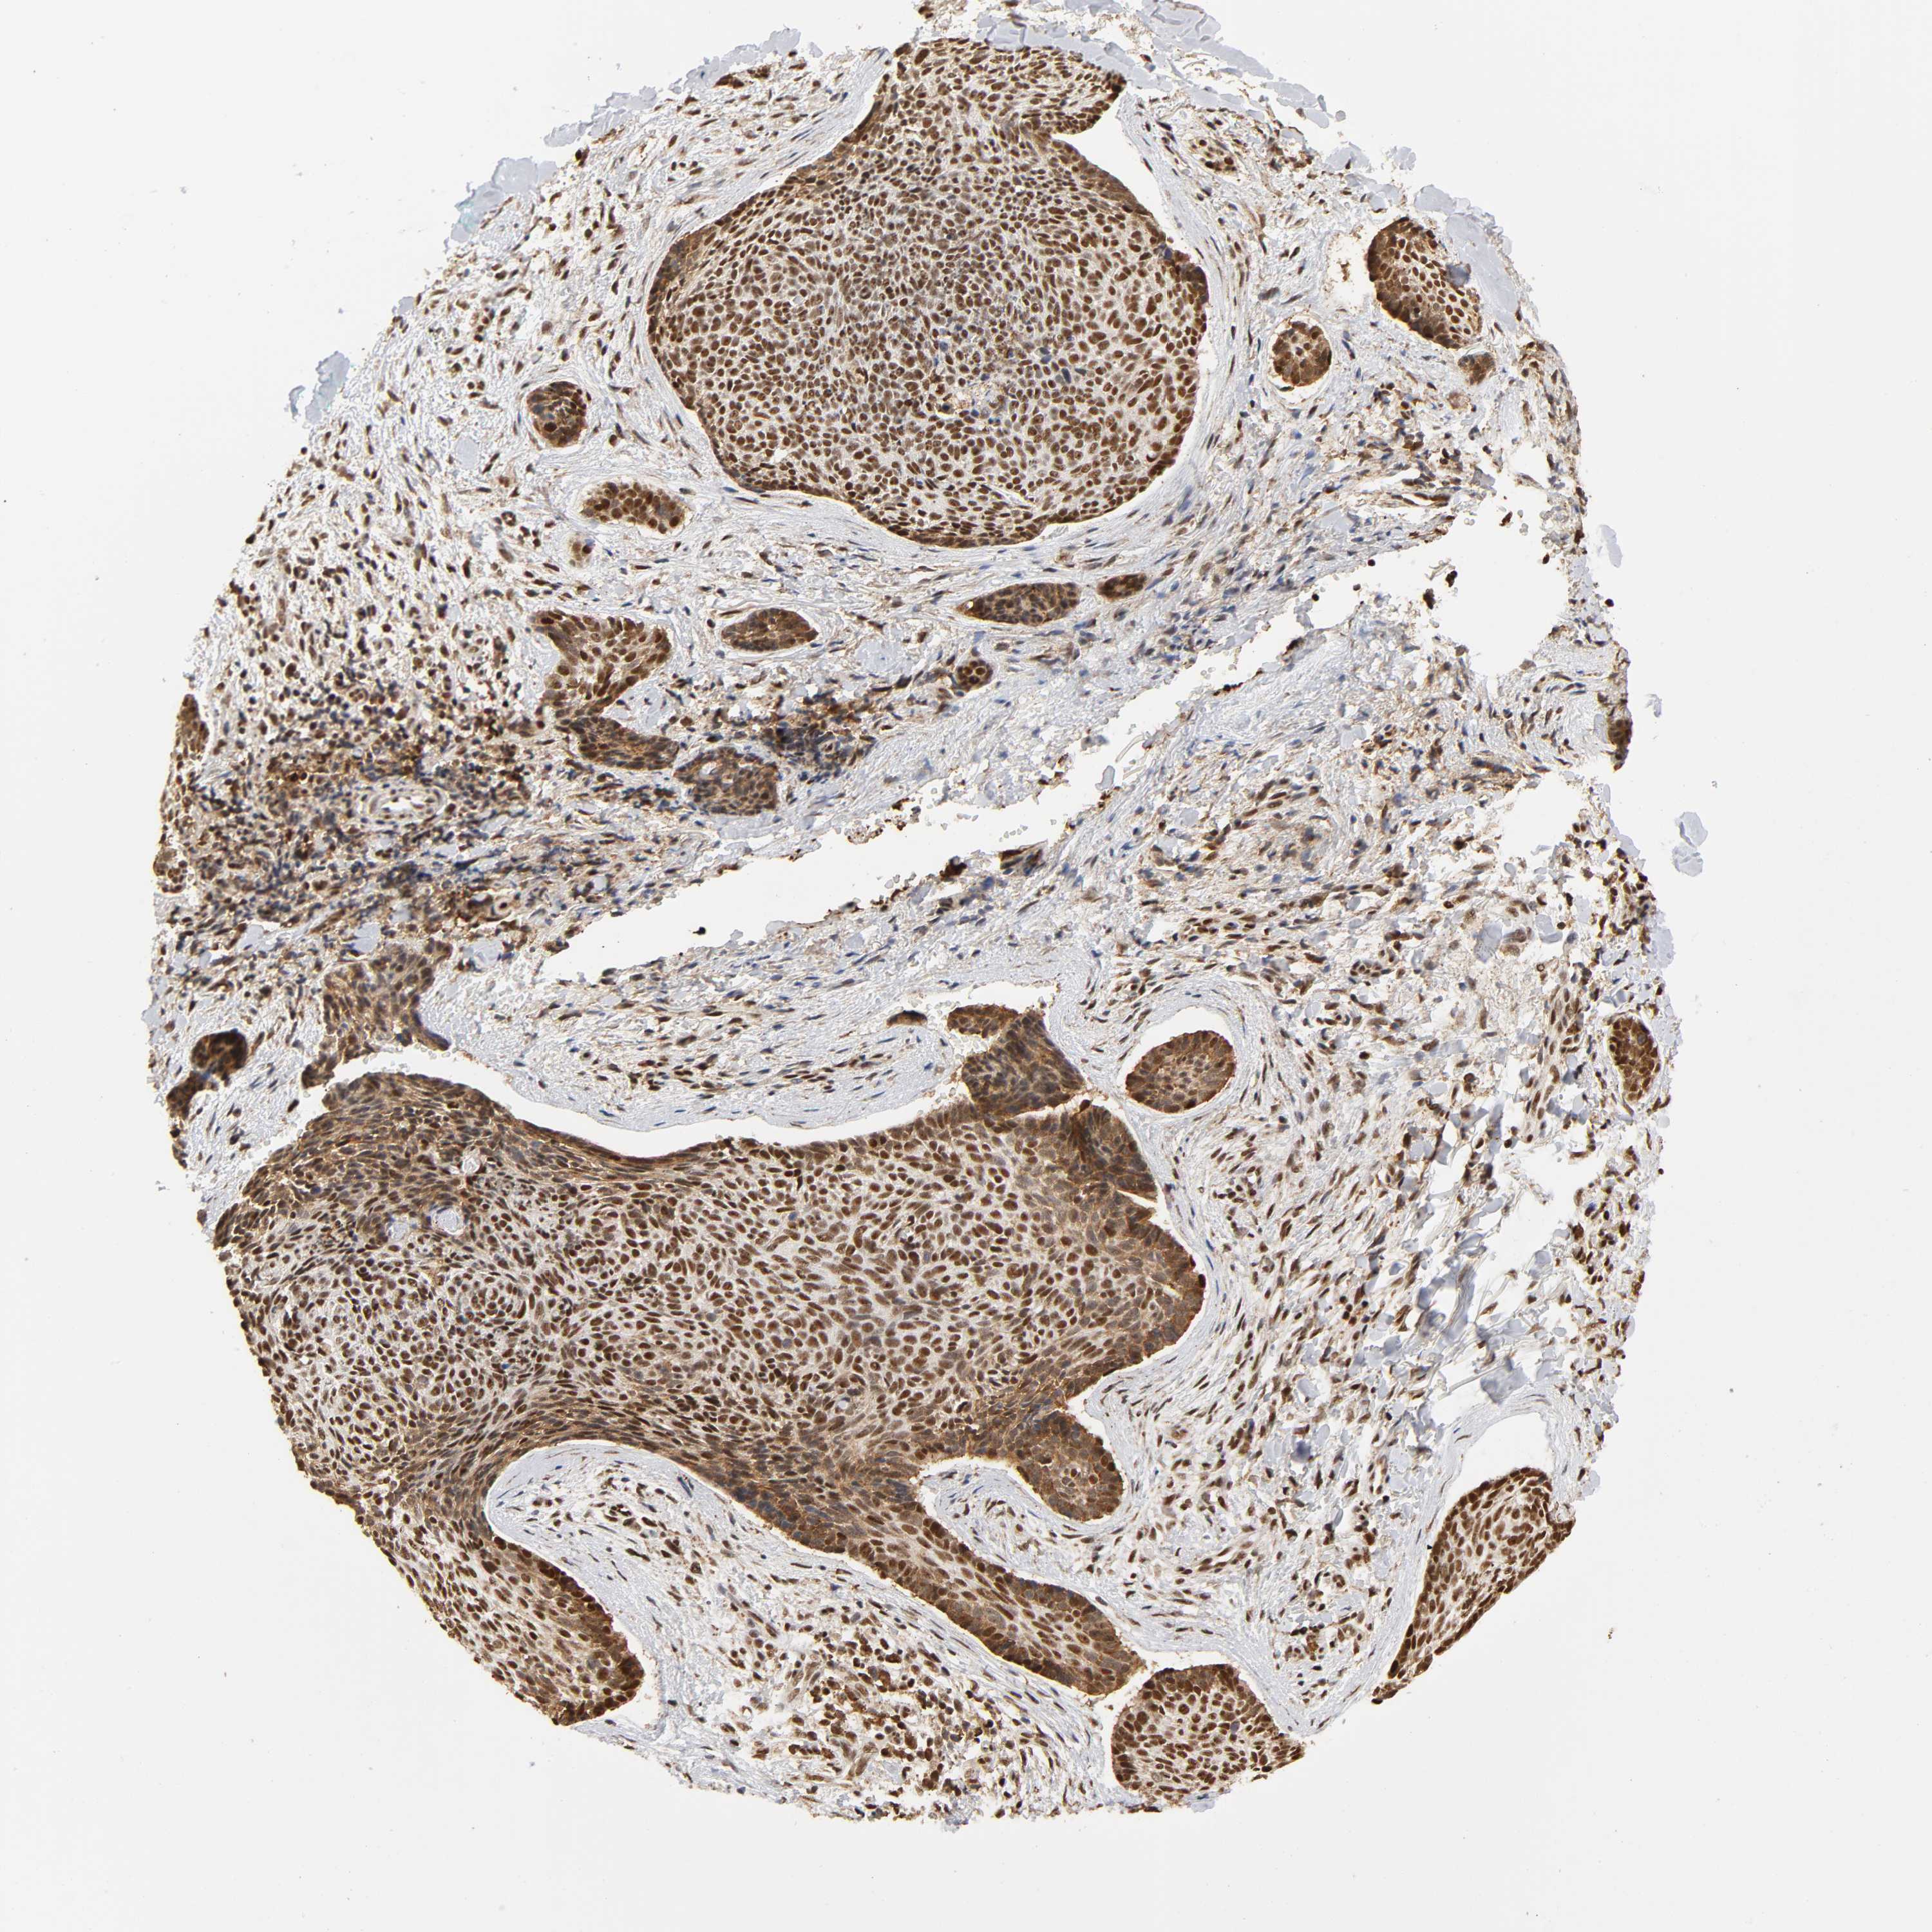

SKIN CANCER - Protein expressioni

A mouse-over function shows sample information and annotation data. Click on an image to view it in a full screen mode. Samples can be filtered based on level of antibody staining by selecting one or several of the following categories: high, medium, low and not detected. The assay and annotation is described here.

Antibody stainingi

Antibody staining in the annotated cell types in the current human tissue is reported as not detected, low, medium, or high, based on conventional immunohistochemistry profiling in selected tissues. This score is based on the combination of the staining intensity and fraction of stained cells.

Each image is clickable and will lead to virtual microscopy that enables deeper exploration of all samples and also displays staining intensity scores, fraction scores and subcellular localization as well as patient and tissue information for each sample.

Antibody HPA003888

Staining

Medium

Intensity

Moderate

Quantity

75%-25%

Location

Nuclear

Basal cell carcinoma